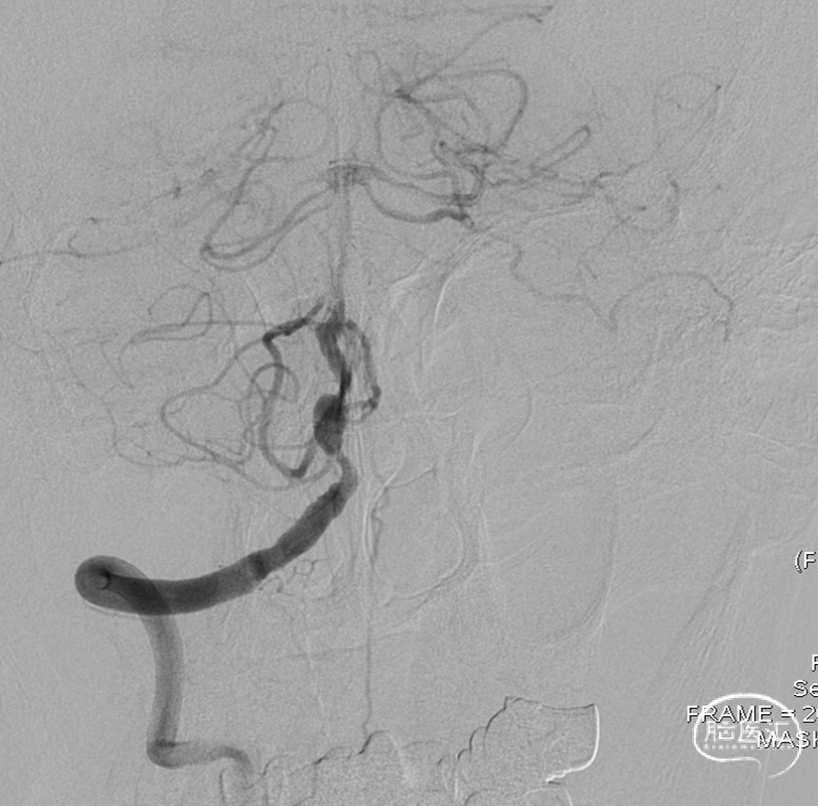

术后即刻DSA。

术后即刻稀释造影:“拉直”可见支架贴壁良好。